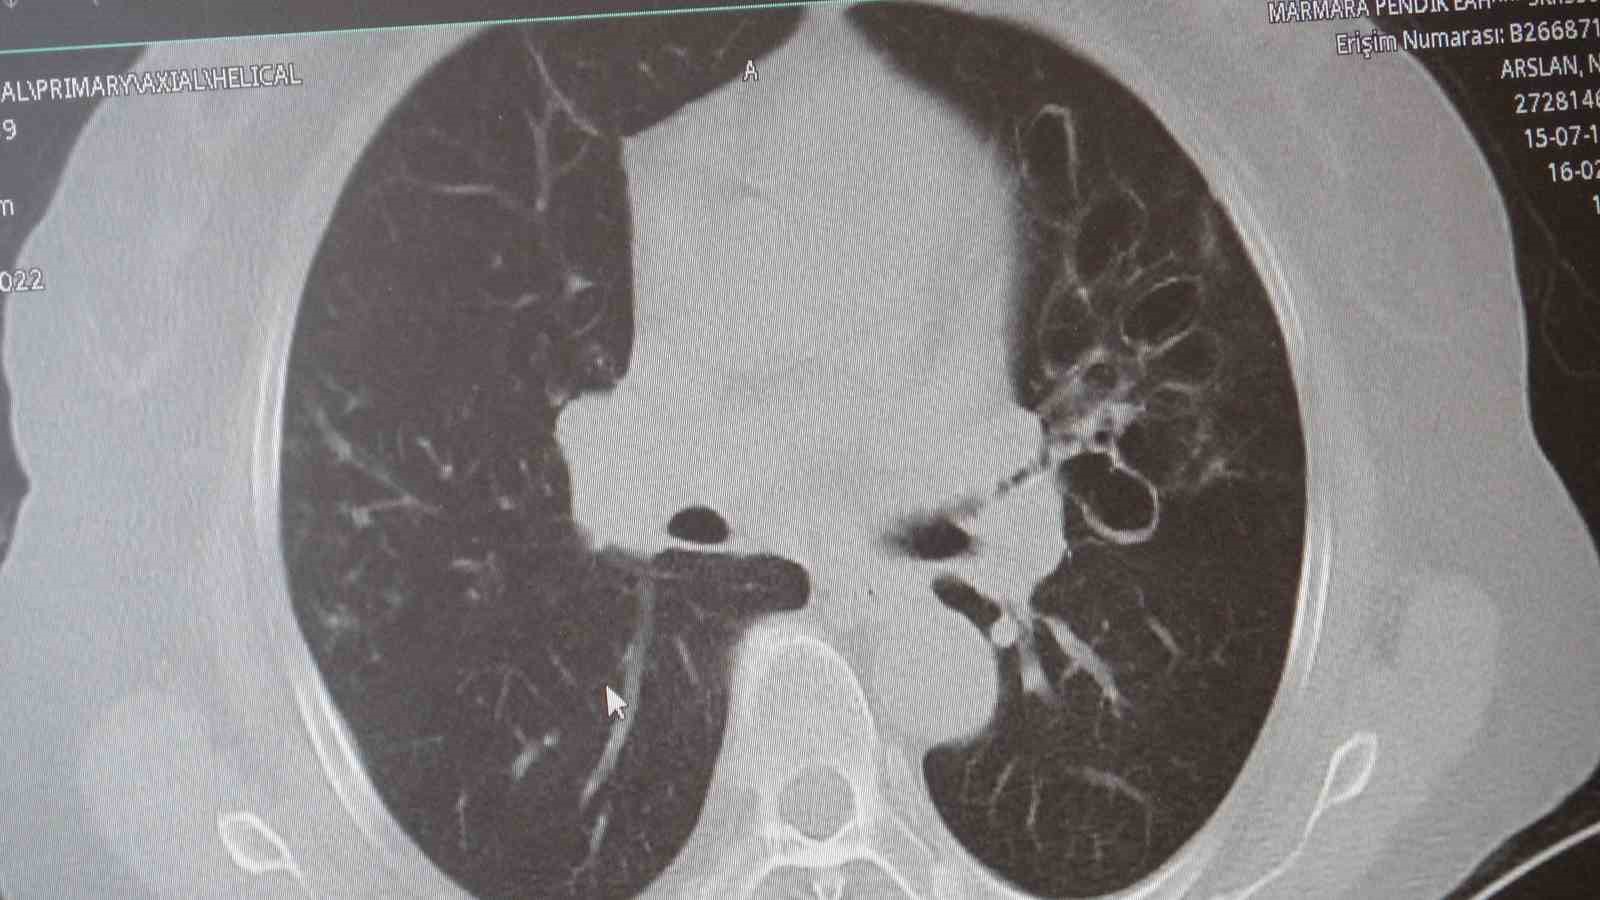

Marmara Üniversitesi Pendik Eğitim ve Araştırma Hastanesi Göğüs Hastalıkları Kliniği’nden Prof. Dr. Sait Karakurt, toplumda sık görülen Kronik Obstrüktif Akciğer Hastalığı (KOAH) ve zatürre hakkında önemli uyarılarda bulundu. KOAH’ın ölümcül hastalıklar listesinde üst sırada yer alan ve toplumda sık görülen bir rahatsızlık olduğunu dile getiren Karakurt, "Vakaların yaklaşık yüzde 85’i sigara kullanımına bağlı" dedi.

Marmara Üniversitesi Pendik Eğitim ve Araştırma Hastanesi uzmanlarından Prof. Dr. Sait Karakurt, dünya genelinde can kayıplarına neden olan hastalıklar arasında 4’üncü sırada yer alan KOAH ve beraberinde getirdiği zatürre riskine karşı önemli açıklamalarda bulundu. Vakaların yüzde 85’inin sigara kullanımı kaynaklı olduğunu vurgulayan Karakurt, KOAH’ın önlenebilir bir hastalık olduğunun altını çizerken; özellikle 65 yaş üstü ve risk grubundaki bireylerin zatürreye karşı aşılama ve erken teşhis konusunda hassas olmaları gerektiğini belirtti.

"KOAH toplumda sık görülen bir hastalıktır ve yaklaşık toplumda bunu yüzde 10 civarında görüyoruz. KOAH, zararlı maddelerin akciğeri parçalamasıyla oluşan bir rahatsızlık ve bunun da en önemli nedeni sigara. Vakaların aşağı yukarı yüzde 85’i sigara kullanımından kaynaklıdır. Bunun dışında hava kirliliği, iş yerlerinde kimyasal maddelere maruz kalma ve enfeksiyonlar da yine KOAH’ın nedenleri arasındadır. KOAH’ın önemi şu; bugün Dünya Sağlık Örgütü’nün (DSÖ) dünyada insanları öldüren hastalıklar listesinde ilk 10’da 4’üncü sırada yer alıyor. KOAH önlenebilir bir rahatsızlıktır; sigaranın bırakılmasıyla birlikte tamamen ortadan kalkacaktır."

KOAH’ın akciğer dokusunu tahrip eden bir hastalık olduğunu ve bu nedenle de hastaların enfeksiyona açık hale geldiğine dikkat çeken Karakurt, "Akciğer dokusunun tahrip olduğu her durumda hastaların enfeksiyona karşı eğilimi artar ve enfeksiyona yakalandıkları zaman bunun geçmesi güç olur. KOAH’lı hastalar zatürre geçirdikleri zaman öksürük ve balgam artışı gibi bir takım belirtiler gelişir. Ayrıca ateşin 38,5 derecenin üstüne çıkması, nefes darlığının artması, titremeyle birlikte ateşin yükselmesi ve bir takım bilinç bozukluğu gibi belirtiler hastanın zatürre olduğunu gösterebilir. Bu nedenle hastaların erkenden doktora başvurmaları önemlidir" şeklinde konuştu.